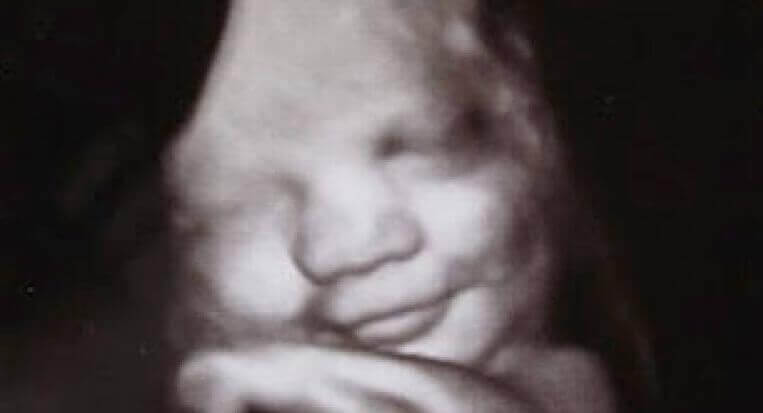

Vain harvat asiat tarjoavat yhtä paljon mysteerejä kuin tunteet. On totta, että ne ovat osa kulttuuriamme, koulutustamme, sukupuoltamme ja maatamme. Ne ovat osa meidän geneettistä perustaamme, ja Durhamin sekä Lancesterin yliopistot ovat suorittaneet mielenkiintoisen tutkimuksen tätä koskien. Tämä tutkimus todistaa, että jo äidin kohdussa oleva sikiö osoittaa pieniä määriä tunteita.

Ultraäänen avulla tässä tutkimuksessa onnistuttiin saamaan selville, että syntymätön lapsi hymyilee, ja osoittaa jopa itkemiseen yhdistettyjä ilmeitä. Tämä todistaa, että jopa rauhallisessa ja hiljaisessa maailmankaikkeudessa, kohdussa, me ihmiset alamme ”aktivoitumaan”. Me alamme harjoittamaan tuota vaistonvaraista ja olennaista kieltä, joka takaa selviytymisemme. Pienikin hymy osoittaa hyvinvointia ja tyytyväisyyttä. Itkeminen täyttää tarkoituksensa tehokkaana ”hälytysjärjestelmänä”. Tämän avulla vauva voi ilmaista kaikkein perusteellisimmat tarpeensa.